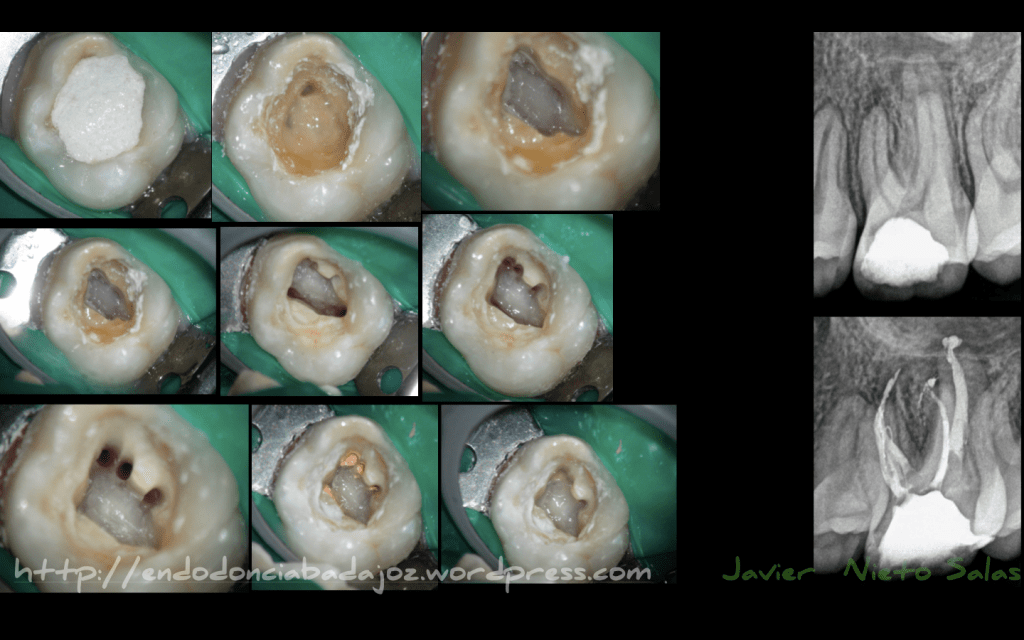

Acude a nuestra consulta un paciente referido con la apertura de la pieza 3.6, se la había realizado en el extranjero.

En la secuencia fotográfica y radiográfica del caso, podemos ver que en el diagnóstico inicial, vemos un par de limas separadas, y una gran apertura con una línea de fisura distal que no sabemos su alcance. Siendo, estas dos situaciones las que me van a determinar el pronóstico del caso:

a) si la línea de fisura la podemos eliminar, con lo que eliminaríamos una entrada de bacterias en los conductos

b) si las limas separadas no nos bloquean el sistemas de conductos y podemos eliminar todo el tejido necrótico y bacteriano del mismo.

Así pues, consideramos «a priori», un tratamiento incierto, con un pronóstico sin determinar. Se trata de una Periodontitis Apical Sintomática.

Instrumentamos los conductos con el Sistema Mtwo, con una conicidad de 25.6%, y la técnica de obturación que usamos fue una Condensación vertical con ola continua de Buchanan modificada. Hacemos un sellado coronal con composite fluido.

Se eliminó la linea de fisura distal con las fresas de tugsteno Munce. Siendo esta su secuencia fotográfica:

Se le aconseja al paciente el uso de «férula de descarga». Pues en este caso, va a determinar el éxito o fracaso si la linea de fisura la hemos conseguido eliminar completamente y si sigue sobrecargando la pieza.